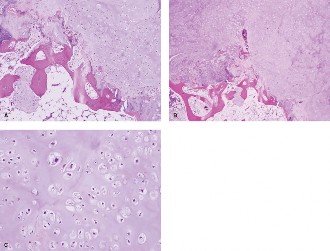

The best answer is (C). The biopsy is a critical step and should be done with the coordination of the treating surgeon who will resect the tumor. The biopsy tract needs to be resectable at the time of definitive surgery. Errant biopsies can lead to contamination of the field and spread of the tumor resulting in increased morbidity and mortality. When biopsies done at referring institutions are compared to those done at treatment centers, Mankin showed that errors in diagnosis, 27.4% versus 12.3%, were significantly higher as were the adverse effects on outcome, 17.4% versus 3.5%. Excisional biopsy is reserved for small superficial tumors. A core needle biopsy is performed by interventional radiology, after the biopsy trajectory was discussed with the surgeon. The following are histologic images of the biopsy (Figs. 1–18A–C). The most likely diagnosis is: 1. Liposarcoma

_Figure 1–18_Cartilaginous neoplasm invading through bone into marrow space (A), Highlights bone destruction and abnormal cellularity and atypia within the cartilage tumor (B), Tumor cells exhibit clear atypia (large, middle cell) and occasional binucleate forms (C). Images taken by David M. Meredith MD, Brigham & Women’s Hospital, Department of Pathology.

The best answer is (D). The slides show grade I chondrosarcoma. There is cellular tumor cartilage infiltrating the normal osteoid. Seen are plump nuclei with more than one cell per lacunae.